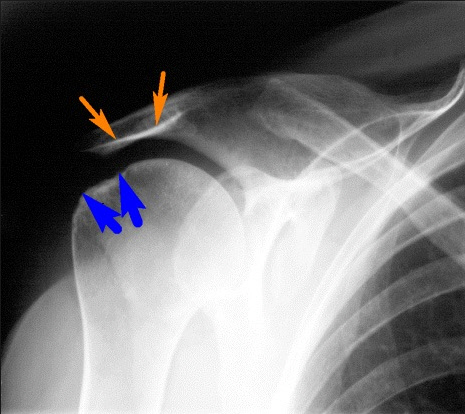

- рентген;

На основании внешнего осмотра, жалоб пациента, результатов инструментальных и лабораторных исследований врач диагностирует ревматоидный артрит плечевых суставов.